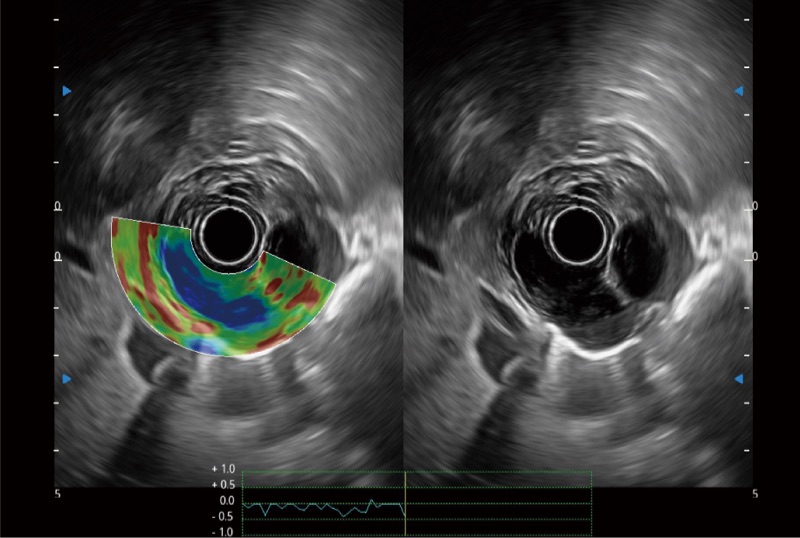

肝左叶和肝静脉的横截面